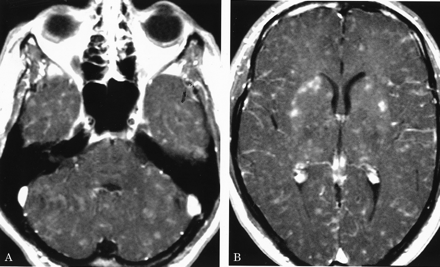

多病灶的幕上的白质病变,包括胼胝体(图1),在所有27个病人,有频繁的参与小脑,中间小脑总花梗,和脑干图1,表)。病变众多,往往是小(3 - 7毫米)但有些小病变成为支流和一些大的(> 7毫米)。19病人实质增强,当明显,导致大脑的粟粒状的外观(图2)。胼胝体的损伤通常是小的,并且涉及中央与周边的相对保留纤维;增强是变量。急性胼胝体的病变(图3)中观察到的活动脑病取而代之的是一个“充满”/穿孔先生出现在后续所有27例(图4),可能代表microinfarctions,没有出现在其他地方。胼胝体,最好在薄片(3毫米厚)矢状T1或T2矢状/质子密度加权图像,由一系列小(3毫米)中央孔相隔7毫米矢状T1和T2矢状/质子密度图像。这些扩展在整个长度的胼胝体。当急性(“雪球”)(见大图3)胼胝体的病变,慢性残余孔较大,尤其是在压部。线性缺陷有时看到的,可能反映microinfarction间接辐射在胼胝体轴突。中央孔(见图4)被认为是由于横向辐射的胼胝体轴突的微型心肌梗塞的可能性。

1991年,我们中的一个(A.D.G.)图像与中央黑洞先生发表在被错误地归因于ADEM的胼胝体。44病人的诊断是不清晰的,回想起来,几乎肯定是党卫军。中央胼胝体的孔女士在党卫军ADEM的不是一个特性或与学生相比,胼胝体的参与女士和亚当在底面的胼胝体隔接口。44尽管胼胝体的任何部分在党卫军可能受到影响,胼胝体的病变通常涉及中央纤维,与外围的相对节约。基于微血管血液供应(图5),44-46⇓⇓microinfarction应该涉及中央的胼胝体纤维。深灰色女士很少参与,但通常发生在儿童外,特别是在丘脑。47Leptomeningeal增强,指出在9我们的27例,与女士或ADEM不发生。

胼胝体病变的大小通常是3 - 7毫米,暗示闭塞的小前毛细管的小动脉中低于100μm胼胝体。44-46⇓⇓这个小尺寸超出动脉造影术的决议,这是几乎总是在SS患者正常。这些胼胝体的微型心肌梗塞的可能性出现最好在3毫米矢状(T1 / T2 /质子密度/天赋)部分,但更大的矢状“雪球”病变也明显的轴向视图(见图3)。